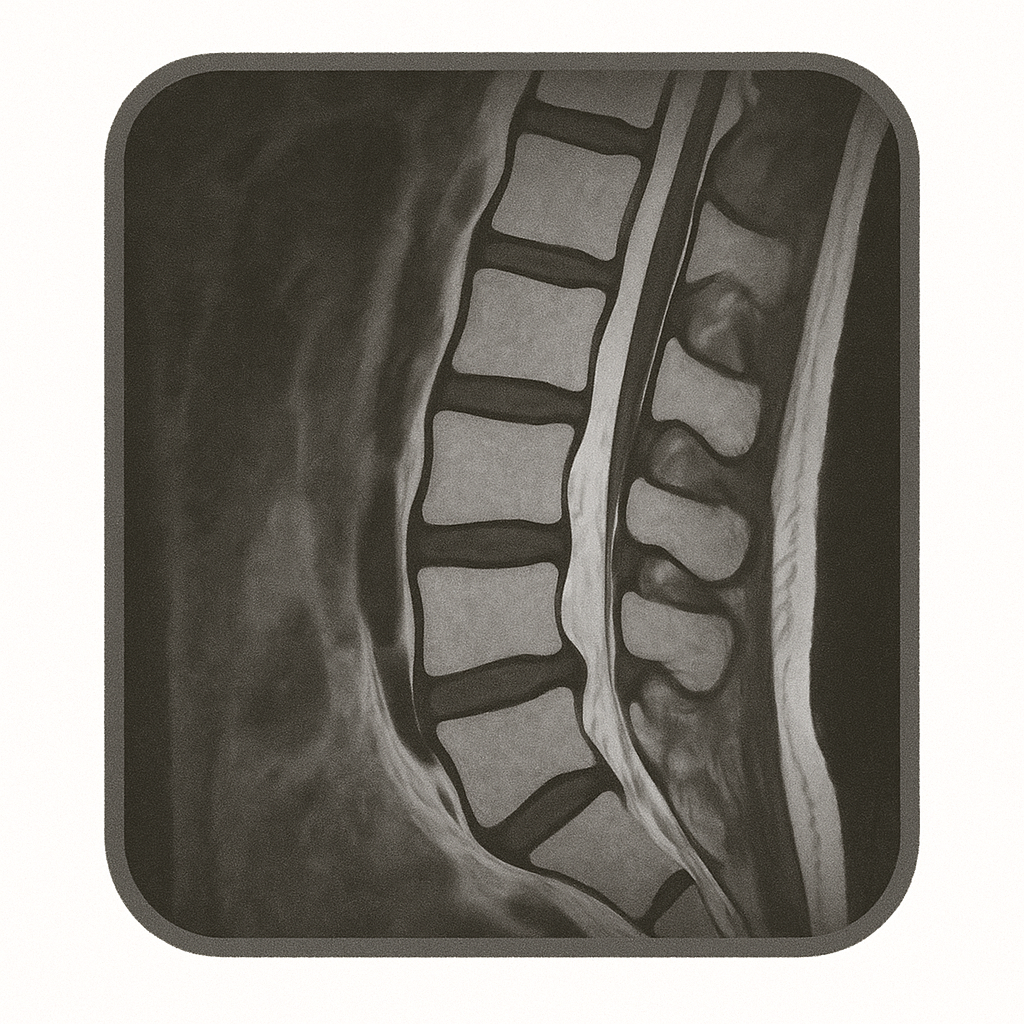

休んでいる時はなんともないのに、立っている・歩いていると、足が痛くなる・痺れる、ということはないでしょうか?

もしかしたら、それは腰部脊柱管狭窄症の症状かもしれません。

今回は、腰部脊柱管狭窄症に関して、解説させていただきます。

背骨の中には、神経が通る「脊柱管(せきちゅうかん)」というトンネルのような構造があります。

加齢などの影響で、この通り道が狭くなり神経が圧迫されて、足に痛みや痺れが出る病気を、「腰部脊柱管狭窄症」と言います。

主に50歳以上の方に多くみられる病気で、男性にやや多い傾向があります。

「歩くと足が痛い・痺れて休みたくなるが、少し休むとまた歩ける」、この特徴的な症状を間欠性跛行(かんけつせいはこう)と呼びます。

・X線(レントゲン)検査

画像にて、骨棘や椎間板腔狭小化の有無を確認します。

・MRI検査

必要に応じて、提携医療機関でのMRI検査を行い、どの部位でどの程度神経が圧迫されているのかを確認します。